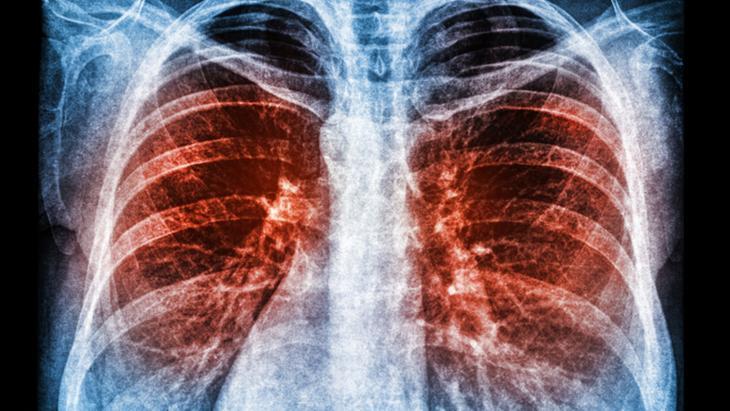

Günümüzde tıbbın ilerlemesi ile birlikte tanı için çeşitli görüntüleme yöntemlerimiz var. Şüphe dahilinde ve hastanın akciğer grafisinde uyumlu belirtiler varlığında hastalarımıza tomografi kontrolleri yapmaktayız. Bu kontroller sayesinde hastalarımız daha erken tanı alabilmektedir. Bu da tedavi başarısını ve hastaların yaşam süresini ciddi şekilde artırıyor” dedi.